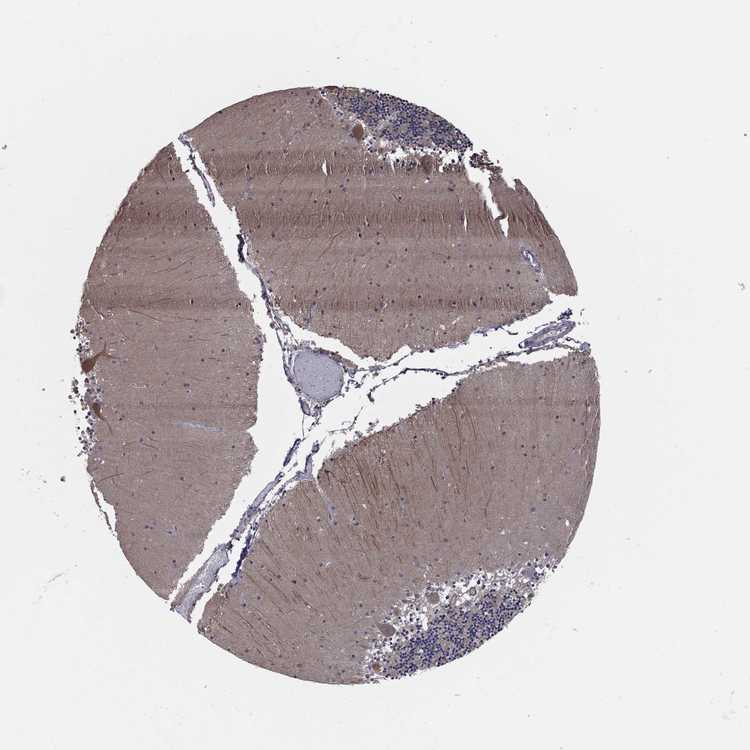

CEREBELLUM - Antibody stainingi

Antibody staining in the annotated cell types in the current human tissue is reported as not detected, low, medium, or high, based on conventional immunohistochemistry profiling in selected tissues. This score is based on the combination of the staining intensity and fraction of stained cells.

Each image is clickable and will lead to virtual microscopy that enables deeper exploration of all samples and also displays staining intensity scores, fraction scores and subcellular localization as well as patient and tissue information for each sample.

Antibody HPA035645Antibody HPA042608

Purkinje cells MediumLow

Cells in granular layer MediumNot detected

Cells in molecular layer Not detectedNot detected